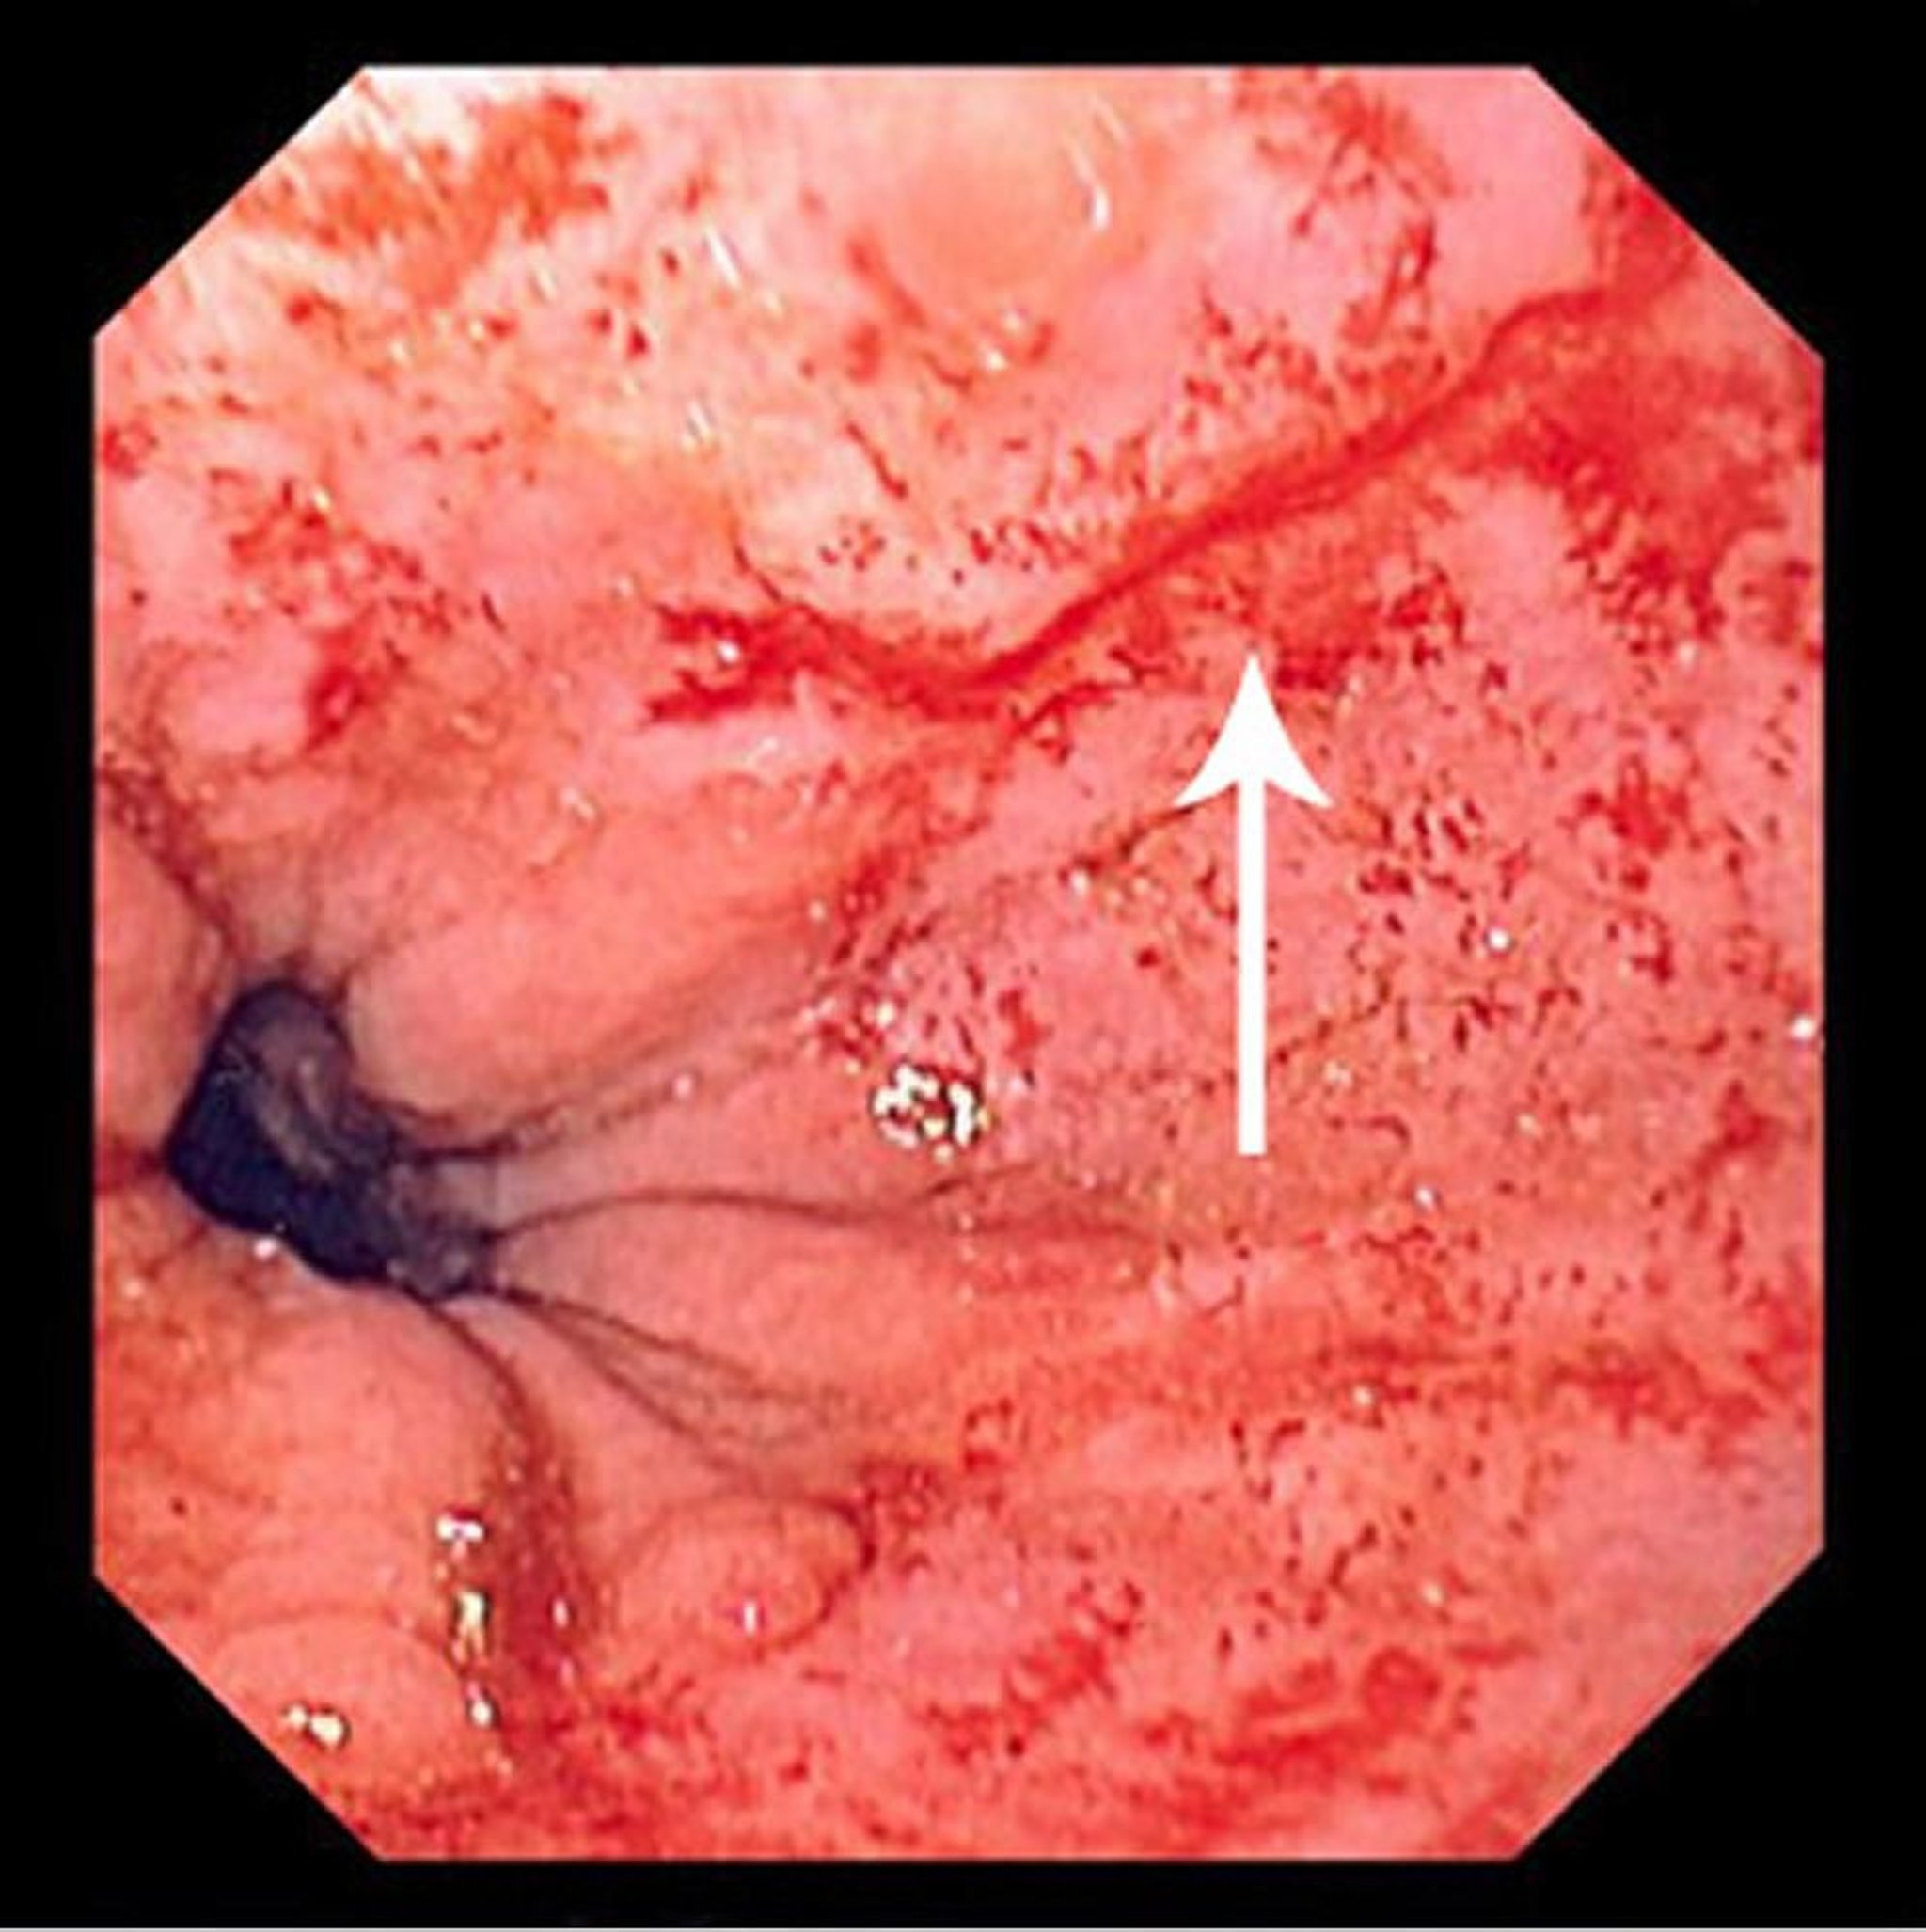

Lacerazione di Mallory-Weiss

Questa immagine mostra una sottile lacerazione di Mallory-Weiss (freccia).

Immagine fornita dal Dott. David M. Martin.